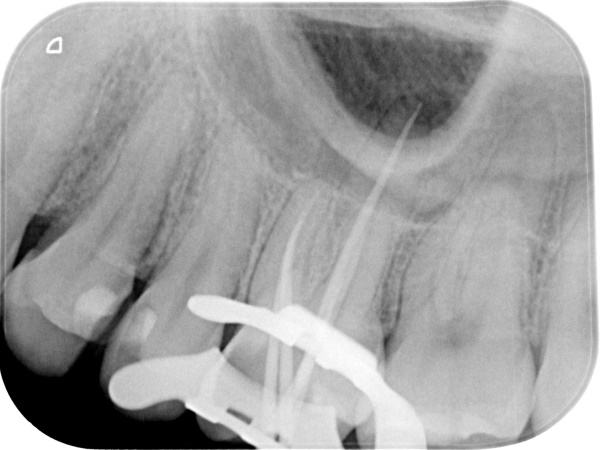

根管治療中(試適時)